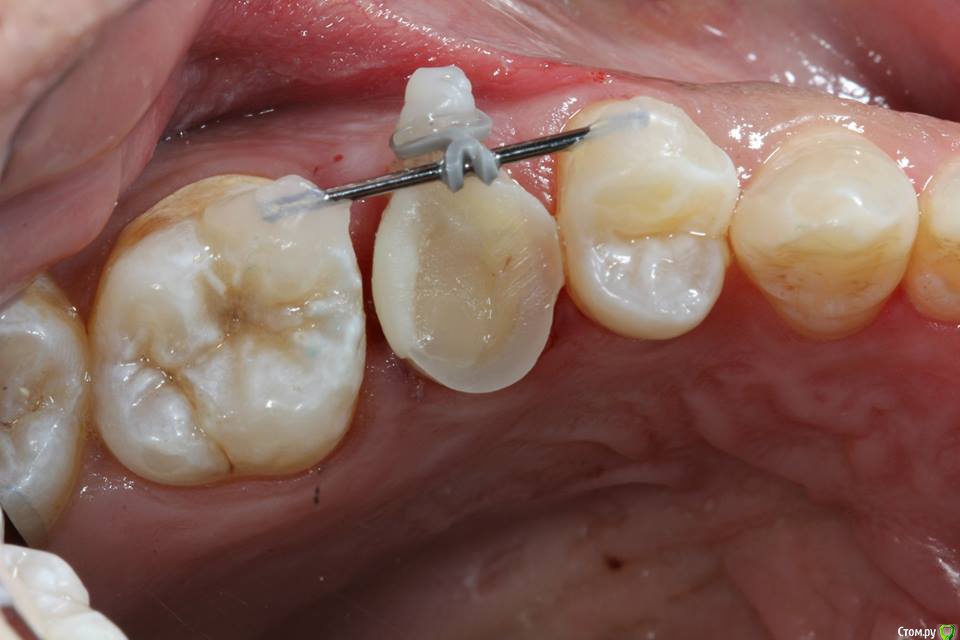

Kolchanov Опубликовано 23 июня, 2015 Поделиться Опубликовано 23 июня, 2015 Экструзия одиночного зуба для получения хоть какого-нибудь феррула. Подозреваю, что процедура не очень сложна и вполне модет быть освоена простым терапевтишкой, т.е. мной. Был бы очень благодарен, если бы кто-нибудь накидал своих мыслей по этому поводу, а еще лучше и фоток. И, конечно же, перечисление материалов. В одной из клиник, где я работаю, делают так иногда.После удаления штифтового зуба имеем поддесневой дефектhttp://s010.radikal.ru/i311/1506/49/4f3a03a5b53b.jpghttp://s010.radikal.ru/i313/1506/55/c752a532f478.jpgПациентка пожелала зуб сохранить. Теперь его тянут. И пятерочку еще в придачу.http://s014.radikal.ru/i327/1506/75/e9897bfb0e24.jpghttp://i024.radikal.ru/1506/99/1f1453b881ef.jpghttp://s017.radikal.ru/i434/1506/ea/caf4284659b4.jpghttp://s018.radikal.ru/i522/1506/ae/b2b54bddcdb8.jpghttp://s015.radikal.ru/i331/1506/7c/0efe752f8c35.jpgПока ничего сложного не вижу.У меня сейчас есть похожий случай. Но, послать в Москву... Не поедут. А на местного ортодонта как-то надежды мало. Я потом залью сюда фотки со своими мыслями. Может кто что присоветует...Спасибо! 1 Ссылка на комментарий

krokomot Опубликовано 23 июня, 2015 Поделиться Опубликовано 23 июня, 2015 Экструзия одиночного зуба для получения хоть какого-нибудь феррула. Подозреваю, что процедура не очень сложна и вполне модет быть освоена простым терапевтишкой, т.е. мной. Был бы очень благодарен, если бы кто-нибудь накидал своих мыслей по этому поводу, а еще лучше и фоток. И, конечно же, перечисление материалов. В одной из клиник, где я работаю, делают так иногда.После удаления штифтового зуба имеем поддесневой дефект Пациентка пожелала зуб сохранить. Теперь его тянут. И пятерочку еще в придачу. Пока ничего сложного не вижу.У меня сейчас есть похожий случай. Но, послать в Москву... Не поедут. А на местного ортодонта как-то надежды мало. Я потом залью сюда фотки со своими мыслями. Может кто что присоветует...Спасибо!Ох и любят у нас врачи заниматься вот таким лепиловом)))) Инженера в себе не скроешь)) Почему не с бреккетами? Приклеили несколько, дугу, цепочку проволку, что угодно, все же проще и предсказуемее (и быстрее) Ссылка на комментарий